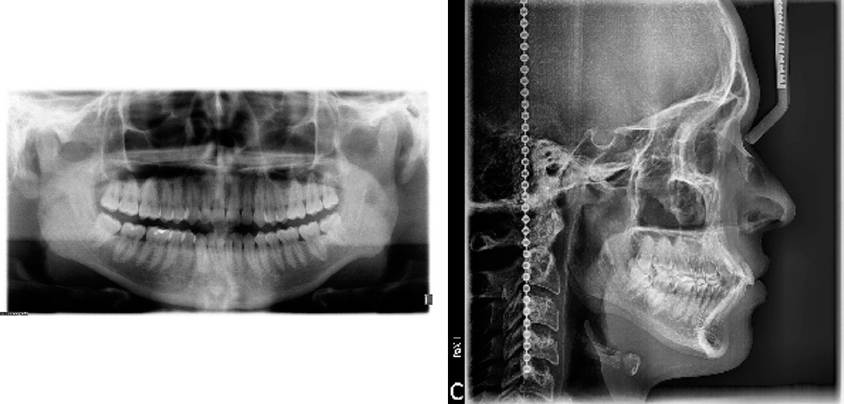

Paciente masculino de 21 años se presentó a la clínica de la Especialidad de Ortodoncia de la Escuela Nacional de Estudios Superiores Unidad León, UNAM. El motivo de consulta fue que sus dientes superiores se encontraban "muy inclinados hacia enfrente". Al analizar la historia clínica y toma de registros fotográficos (Figura 1), imagenológicos (Figura 2) y de modelos de estudio (Figura 3), se diagnosticó lo siguiente: Clase I esquelética, mesofacial, con crecimiento neutro, presencia de todos los dientes erupcionados, clase I molar bilateral, clase II canina derecha y clase I canina izquierda, con apiñamiento leve superior e inferior, protrusión y proclinación de incisivos superiores e inferiores, múltiples giroversiones; con perfil facial recto con proquelia inferior y escalón labial ligeramente negativo. Sin alteraciones ni patologías en la función del aparato estomatognático. El objetivo del tratamiento fue aliviar apiñamiento superior e inferior; corregir la proinclinación y la protrusión de los incisivos superiores e inferiores; distalizar arcada superior e inferior con intrusión del segmento posterior y retroclinación del segmento anterior; conservar la clase I molar, lograr clase I canina bilateral, y retruir el labio inferior.